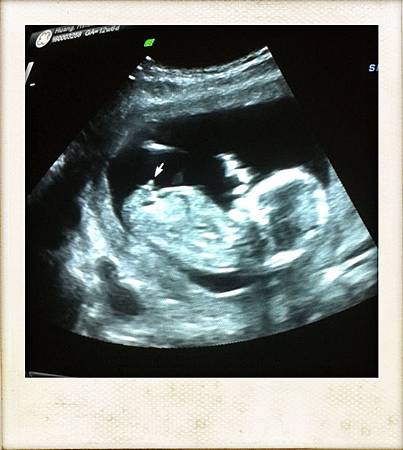

就是利用抽媽媽的血及超音波(ultrasound)看baby頸後透明帶厚度(NT=NuchalTranslucency)來測唐式症(down syndrome)寶寶的機率

於是就躺在超音波的床上,護士小姐要我把肚子那塊”清空”,她再用一條毛巾包塞在褲緣並蓋上另一條在肚子上(個人覺得這幾個動作滿細心的),躺在那仔細觀察環境四週,天花板上還有類似像星星一點一點的燈,彷彿就是躺在那看星星(真貼心),而除了床旁邊那台的大機器的螢幕外,躺著的正前方也有一台電視螢幕可供媽媽看!!可說是有精心設計又有人情味的實驗室啊!!!過了一會兒我們的超音波師就進來那微暗的房間,一大早嚼著口香糖還頂著有點像貝克漢的頭,很有精神的樣子!!而且發我的中文名字非常正確(加分),把毛巾掀開後就把照超音波的膠擠在我肚皮上,記得以前在台灣作超音波都是冰冰的膠,今天這個還熱熱的耶,難不成他們還加熱?真的有用心!!!!於是邊照就邊跟我們解釋,最主是要測baby頸後透明帶厚度,當然也show給我們看baby的頭,兩隻手臂,兩隻腳,心臟等,由於這是我們第一次照這種大台的儀器,所以很精密,看得超清楚的,而且整個就是”人型”出現啊,好奇妙的感覺啊!!!!!!就是有個長得像人的人住在我肚子裡耶~~~~~這個超音波師人算年輕,也滿好聊的,他一看猜這是我第一胎,每個畫面都令我那麼驚喜,他也放了baby的心跳聲給我們聽,果然跟之前在醫院手提式超音波聽的聲音有差,今天這個超~大~聲!!都快要有回音的感覺了…邊照邊看他就說依目前的畫面來看,整體都表現非常健康,也給我們看腦部,解釋中間有一條像線的的區隔,就是分左腦右腦,目前也正還在發育中,這個畫面也有讓我驚喜到!!!我問他可否用我手機拍一些畫面,他也都ok,不過lab本身也有準備列印及光碟給我們帶回家(真好)!!看完一般超音波還轉換成4D的超音波show給我們看,天啊!!!!!!!!又是真是震撼人心的畫面….我沒有想到那麼小可以看得如此清楚耶!!!手啊腳啊頭啊…反正就是驚喜連連…….而且兩隻手還握在頭前方,像是在沈思一樣,太妙太妙了!!!